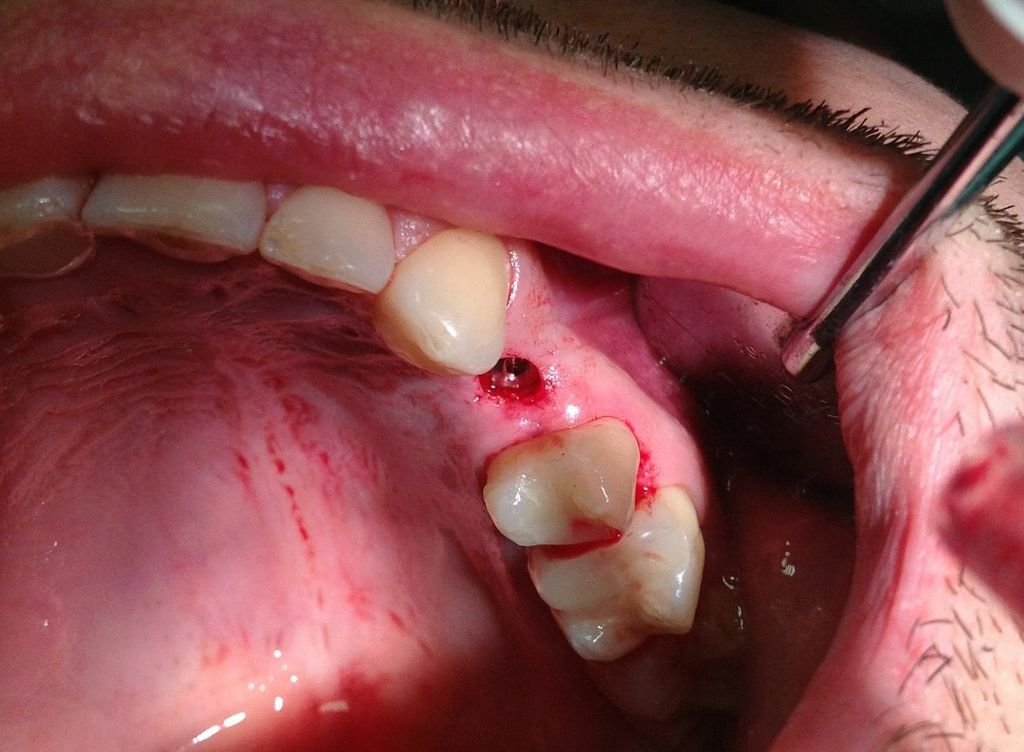

Presentazione del Caso:

Il paziente si presenta alla mia attenzione lamentando ipersensibilità dentinale e recessione antiestetica in zona 23.

Dopo valutazione dell'altezza e dello spessore adeguato di gengiva aderente e fornice sufficientemente profondo a livello della recessione (1a classe di Miller) si opta per l'intervento di spostamento coronale di lembo a spessore misto, senza innesto.

(Intervento e foto eseguiti da me in 1h)